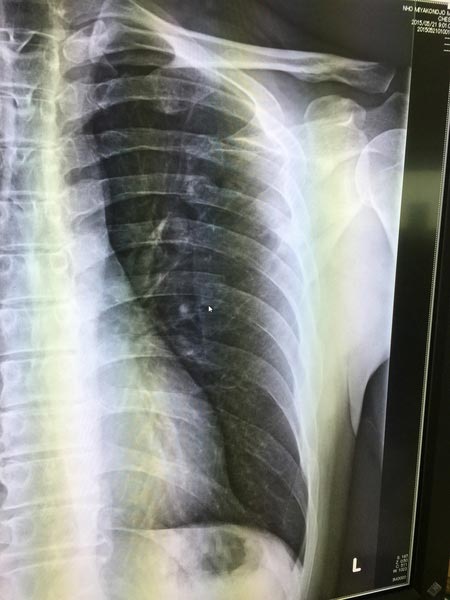

去年バイクで転倒してしまい、肩甲骨と肋骨を折っていました。

肋骨は2月頃に繋がってきましたが、なかなか肩甲骨が・・・

本日の検査で、少し骨が付き始めていました。